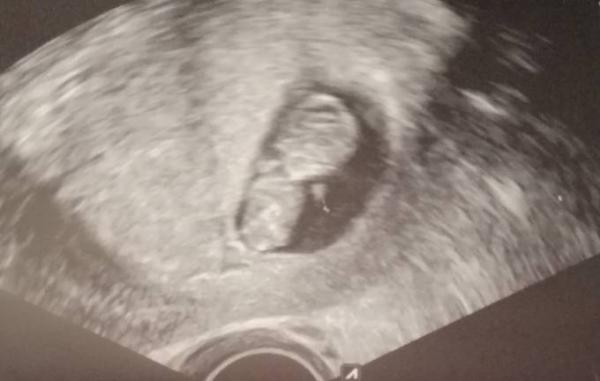

Es hat kräftig gezappelt. Alles dran was soll Jz können wir es den kindern u Schwiegereltern auf Weihnachten sagen. Es hat sogar aufgeholt. Letztes wurde ich drei tage zurück datiert jetzt ist es nur noch ein tag,

Bild zu Baby geht es gut - Forum für Juli - Mamis